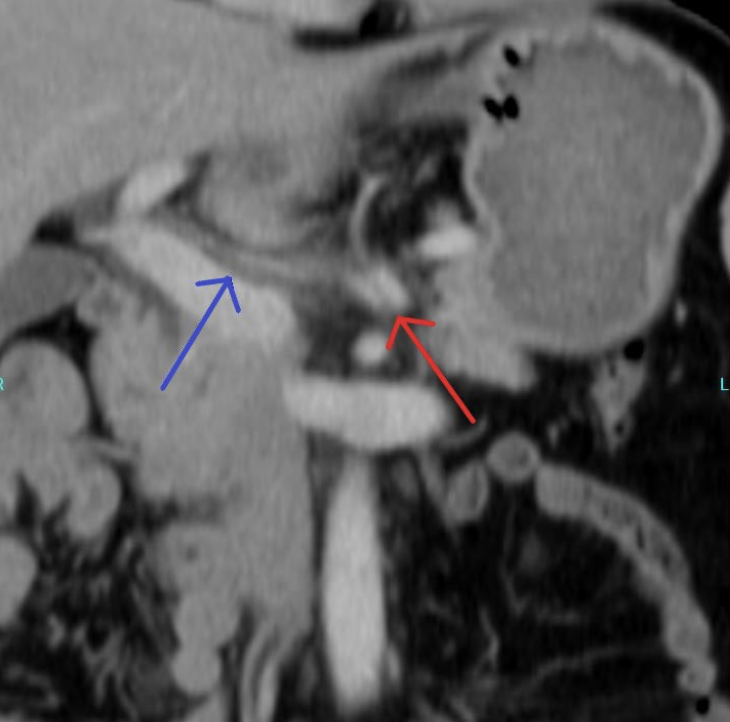

A contrast-enhanced CT scan was completed and revealed stenosis of the celiac trunk and mild bulbous dilatation of the post-stenotic celiac trunk (Figure 1). There was the appearance of a dissection flap that developed into an eccentric hypodense non-enhancing false lumen. This appeared to extend into the common hepatic arterial trunk and the splenic arterial branch, then continued to the splenic hilum (Figure 2 and Figure 3). In addition, there was a large splenic hypo-density involving almost one-third of the central spleen (Figure 4). The findings were consistent with an acute dissection of the splenic and hepatic arteries, along with splenic infarction of the central one-third of the spleen. A differential diagnosis of arcuate ligament syndrome was also considered, given the significant scoliosis seen on scout film of the CT scan (Figure 5).